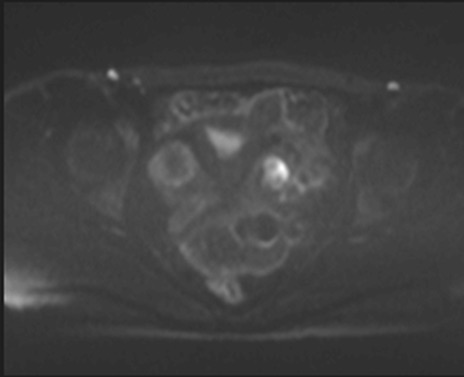

症例39 DWI/ADC

MRI(4日後)